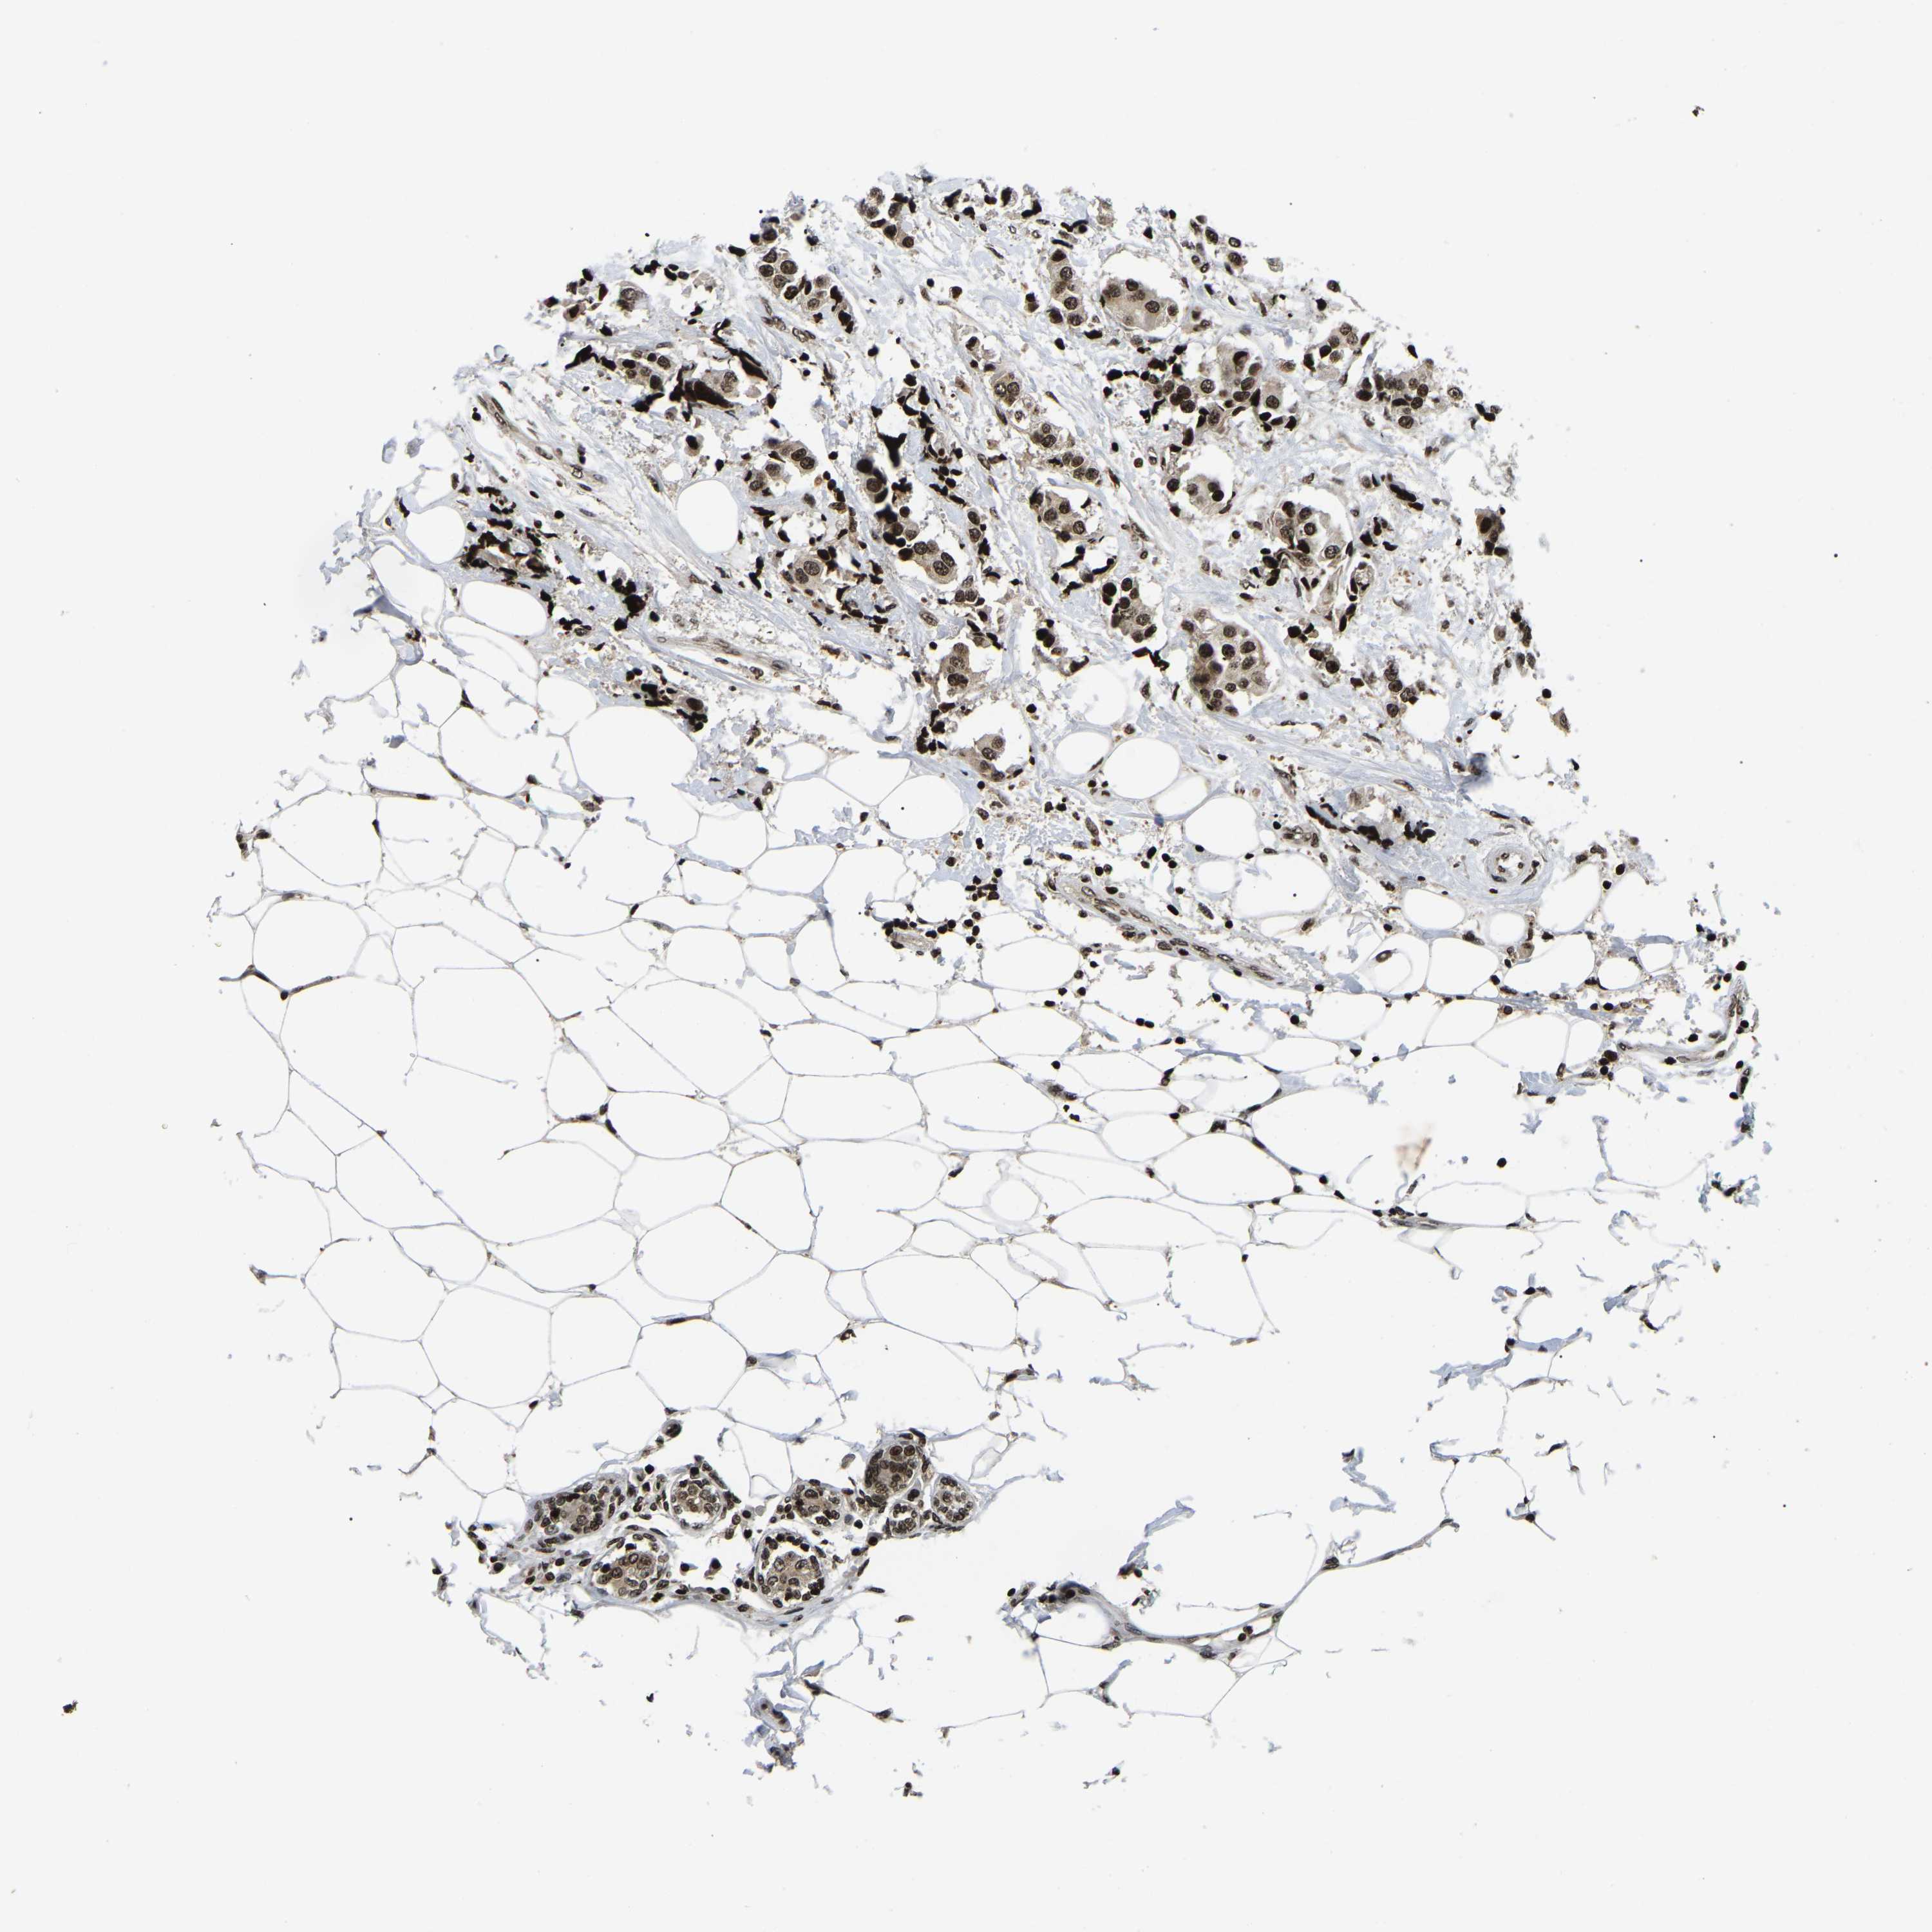

BRCA TCGA BRCA VALIDATION PROTEIN EXPRESSION

ANTIBODIES

AND

VALIDATION